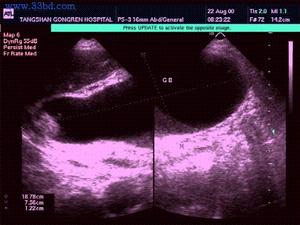

急性膽囊炎--B超當醫生檢查病人的腹部時,可以發現右上腹部有壓痛,並有腹肌緊張,大約在1/3的病人中還能摸到腫大的膽囊。化驗病人的血液,會發現多數人血中的白細胞計數及中性白細胞增多。B超檢查可發現膽囊腫大、囊壁增厚,並可見結石堵在膽囊的頸部。

3.B型超聲檢查,膽囊增大,囊壁增厚,可能可看到結石的影像。

3.B超檢查示膽囊增大,壁厚>3.5mm,內有強光團伴聲影。